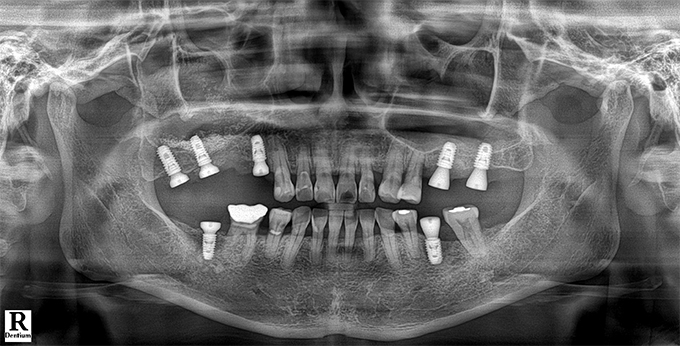

Before & After

임플란트 전후사진

before

2022.11.24

After

2022.12.09

※ 상기 치료전후 사진은 환자의 동의 하에 게재되는 것이며 동일한 촬영각도로 촬영 하였고 치료 기간을 명시하였습니다.

이러한 치료의 결과는 이 환자분에게만 해당되는 것이며 환자의 상태에 따라 똑같은 결과를 얻지 못할 수도 있습니다.

환자분의 상태에 따라 치료 기간, 효과 및 부작용은 상이할 수 있습니다.

치료전후 사진 게재는 의료법 제 23조, 제56조에 의거하여 게재합니다.